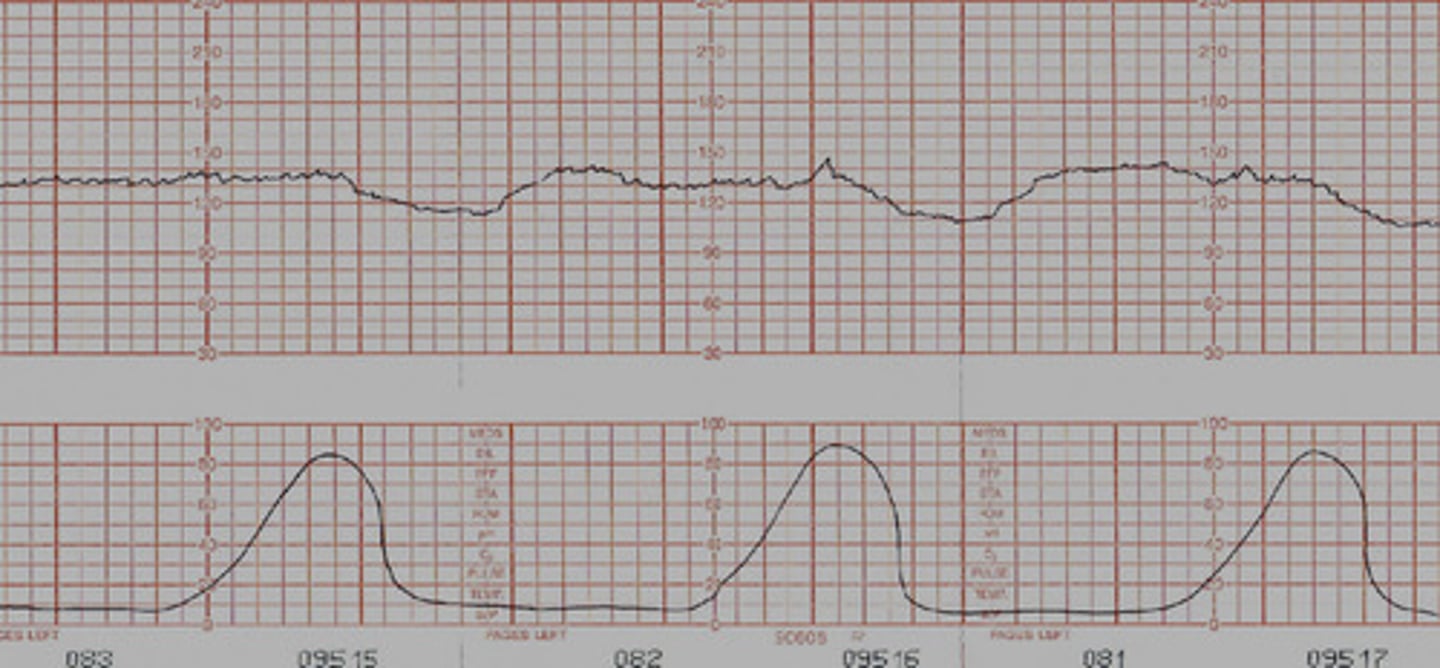

Early decelerations

Caused by head compression usually as head gets lower in cervix: typically a good sign

- Mirror image of contraction

Late decelerations

caused by uteroplacental insufficiency: NOT GOOD

- happens after contraction

- need to give O2, fluid, and change position

- notify provider